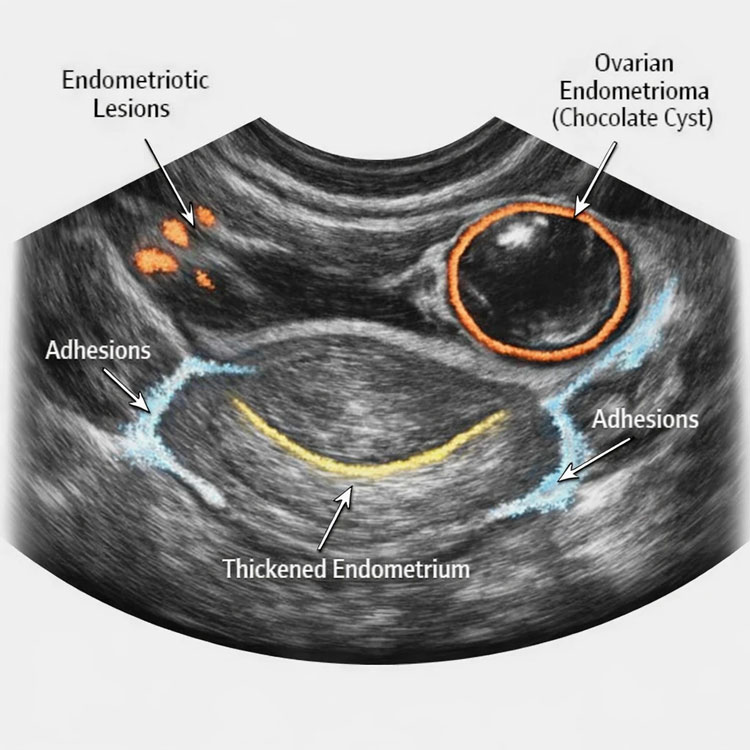

۳. ارزیابی میزان چسبندگی لگنی (بررسی Sliding Sign)

در لگن یک فرد سالم، اندامها (مثل رحم و روده) به راحتی روی یکدیگر میلغزند. در سونوگرافی آندومتریوز، پزشک با اعمال فشار ملایم با پروب سونوگرافی، لغزندگی اندامها را بررسی میکند (علامت لغزش یا Sliding Sign). اگر اندامها به هم چسبیده باشند و نلغزند، نشاندهنده چسبندگی شدید ناشی از آندومتریوز است. این کاربرد یکی از مهمترین برتریهای سونوگرافی نسبت به امآرآی (MRI) است، زیرا سونوگرافی یک روش پویا (داینامیک) است.